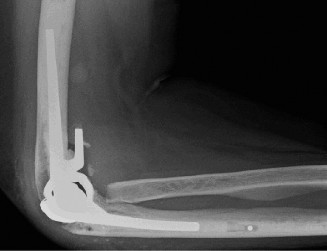

A radiograph of the patient is shown in Figure 2–68. Based on the information obtained thus far, what is the most likely classification of this injury?

🔍 Click to enlargeClinical Radiograph / Orthopedic Image

Figure 2–68

The correct answer is (D). Based on the amount of distance between the coracoid process and the clavicle (CC interspace); the fact that the distal clavicle is tenting the skin and that the joint is irreducible, this AC joint separation can best be classified as a type V. The remaining answer choices are incorrect based on the information provided in Table 2–10 describes the Rockwood classification of AC joint injuries.